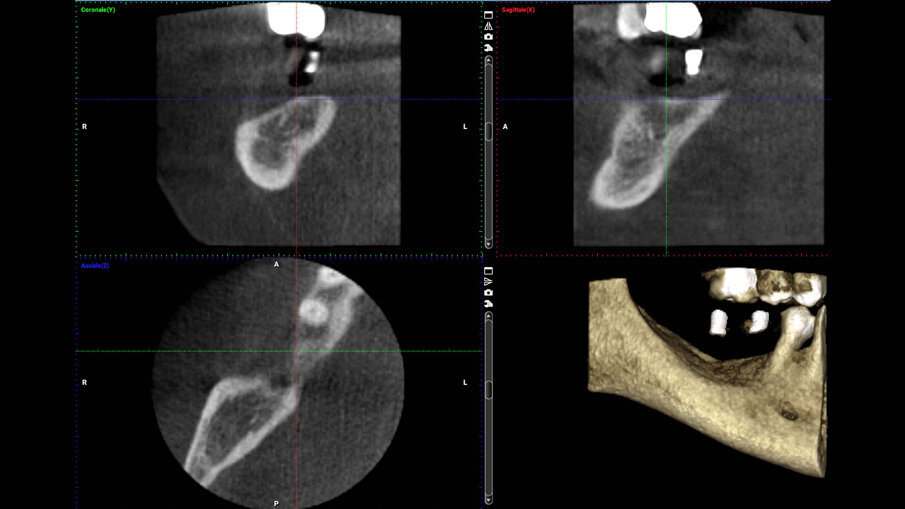

Nell’area edentula mandibolare, erano visibili un deficit osseo orizzontale e verticale che necessitava di una rigenerazione ossea ma che avrebbe permesso l’inserimento contestuale di impianti endossei (Figg. 1a-1c). La paziente, dopo valutazione delle alternative terapeutiche, sceglieva di eseguire una rigenerazione ossea protetta con l’utilizzo di una griglia in titanio customizzata contestualmente all’inserimento implantare. In una seduta successiva, venivano quindi rilevate delle impronte e veniva costruita una ceratura diagnostica con denti di dimensioni e posizione ideale per ottenere corretti rapporti intra- e inter-arcata e, successivamente, una dima diagnostico-radiologica con reperi radio-opachi, utilizzata per l’esecuzione di una CBCT.

Figg. 1a-1c_Foto clinica e sezioni di CBCT iniziali in cui si evidenzia edentulia distale all’elemento 4.5 con atrofia tridimensionale.